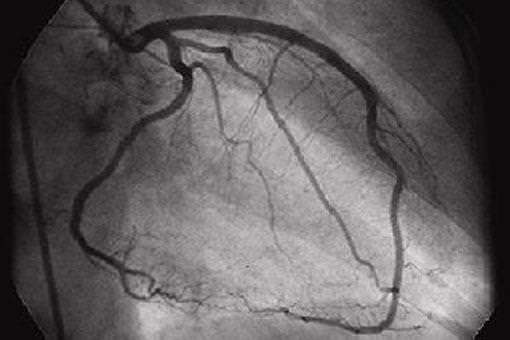

Se si valuterà la necessità di approfondire con esami di secondo livello, il cardiologo può richiedere: l’ecocardiogramma c/d, l’ecodoppler dei vasi epiaortici, test da sforzo, scintigrafia miocardica, tc cuore, RM o la coronarografia.